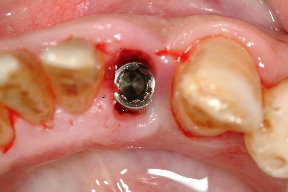

圖三為拔除之下顎側門齒,可見牙根處仍有許多的牙結石,因此治療無望,圖四為立即植牙後的情形,這時流血已完全停止,而齒槽骨與人工植第之縫隙再使用合成人工骨粉修復之,圖五為一週後牙肉之恢復情況

圖三 |

圖四 |